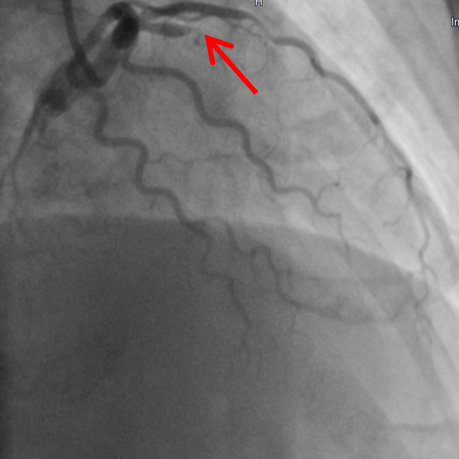

Akuter Herzinfarkt mit Verschluss des Vorderwandgefäßes (Bild 1a - Pfeil). Nach der Wiedereröffnung und dem Einsetzen einer Gefäßstütze kontrastiert sich das Gefäß wieder in ganzer Länge (Bild 1b).